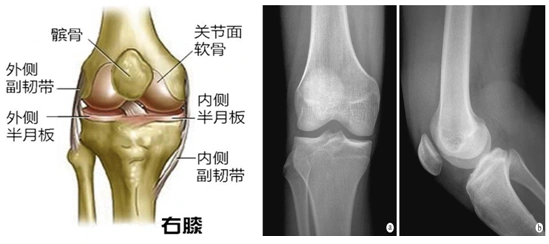

人工膝关节术后健康教育

膝关节(骨结构)

膝盖是人体最大最复杂的关节,膝关节属于铰链关节,它是我们身上少数

同时也是主要负重关节,因此它的结构失常可影响膝关节的正常力学平衡

产生一个牵拉韧带与髌骨的力,从而相杠杆一样带动胫骨围绕膝关节运动